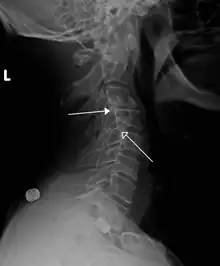

X-ray picture of a grade 1 isthmic anterolisthesis at L4-5

MRI of L5-S1 anterolisthesis- X-ray of a grade 4 anterolisthesis at L5-S1 with spinal misalignment indicated

Retrolisthesis

A retrolisthesis is a posterior displacement of one vertebral body with respect to the subjacent vertebra to a degree less than a luxation (dislocation). Retrolistheses are most easily diagnosed on lateral x-ray views of the spine. Views, where care has been taken to expose for a true lateral view without any rotation, offer the best diagnostic quality.

Retrolistheses are found most prominently in the cervical and lumbar region, but can also be seen in the thoracic area.